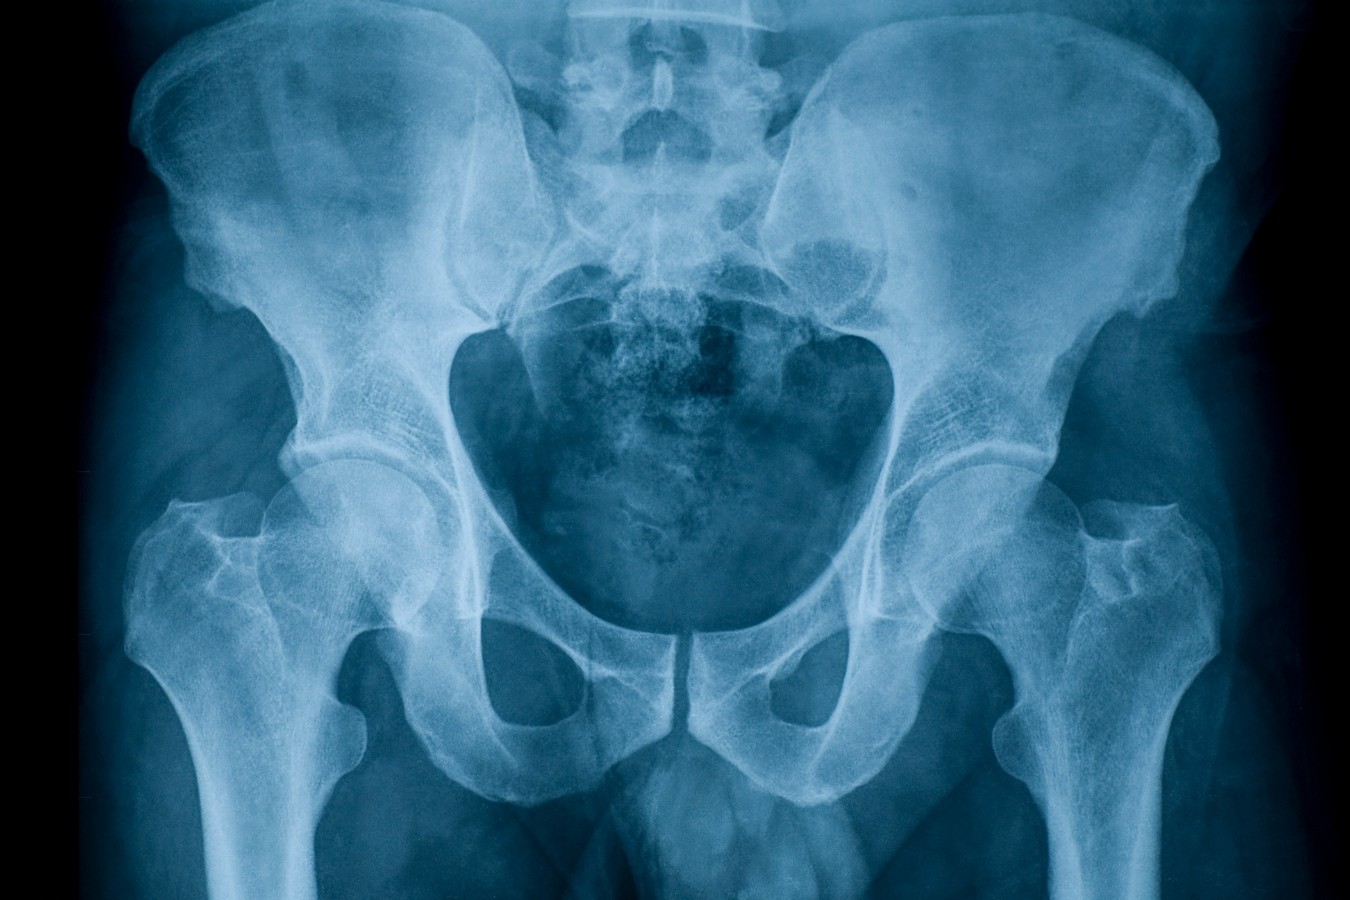

In this article, we look at the causes of back pain in the first, second, and third trimester, and ways to relieve the pain. In fact, more than 80 percent of adults, according to one survey, have a problem with lower back pain at some point in their lives, and a large percentage have pain that is. Back pain is one of the most common reasons people visit a doctor. Pain is something everyone has dealt with in their lives. Here's what to look out for. Vaginal pain is common throughout all stages of pregnancy. Here, learn about the link between breast pain and pregnancy, as well as treatments. Breast pain is common before a period, but it can also signal pregnancy. If you're feeling right side pain during pregnancy this list may help you discover the possible causes and treatments for your. Gas pain is common during pregnancy. Learn about the causes and treatment of uterus pain in early pregnancy here. Consider seven ways to relieve back pain during pregnancy—from good posture and physical activity to complementary therapies. Uterus pain in early pregnancy is a common experience, and i.

In this article, we look at the causes of back pain in the first, second, and third trimester, and ways to relieve the pain spd pregnancy. Here, learn about the link between breast pain and pregnancy, as well as treatments.